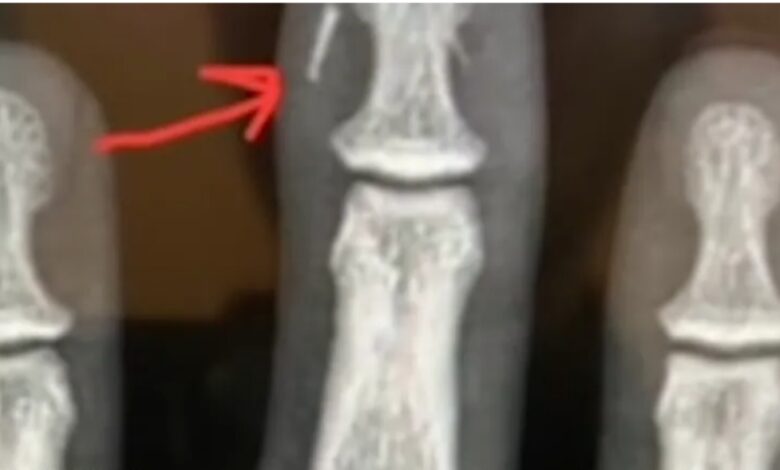

و كشف أيضا أن الإصابات التي تكون نتيجة للرصاص ، يتم فحصها فإذا كانت الرصاصة مستقرة بالعظم ولا تتحرك ، يتم مراقبتها وإذا إستمرت على هذا الوضع لا يتم إزالتها بالجراحة ولاكن في حالة حركتها تكون الحالة خطيرة ويجب التدخل فورا .